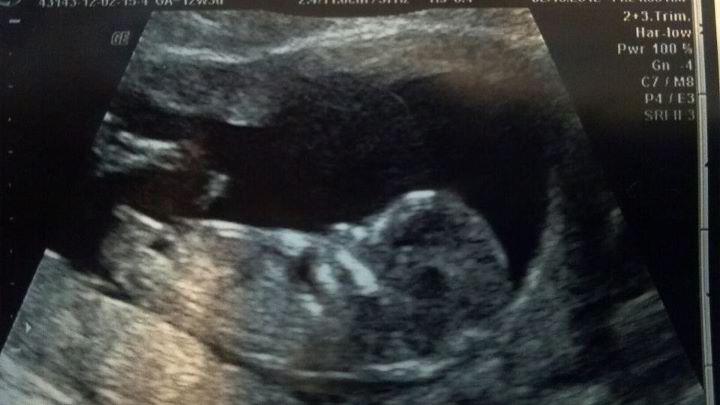

Congratulations on your pretty princess :)

Congrats on your sweet little girl :)